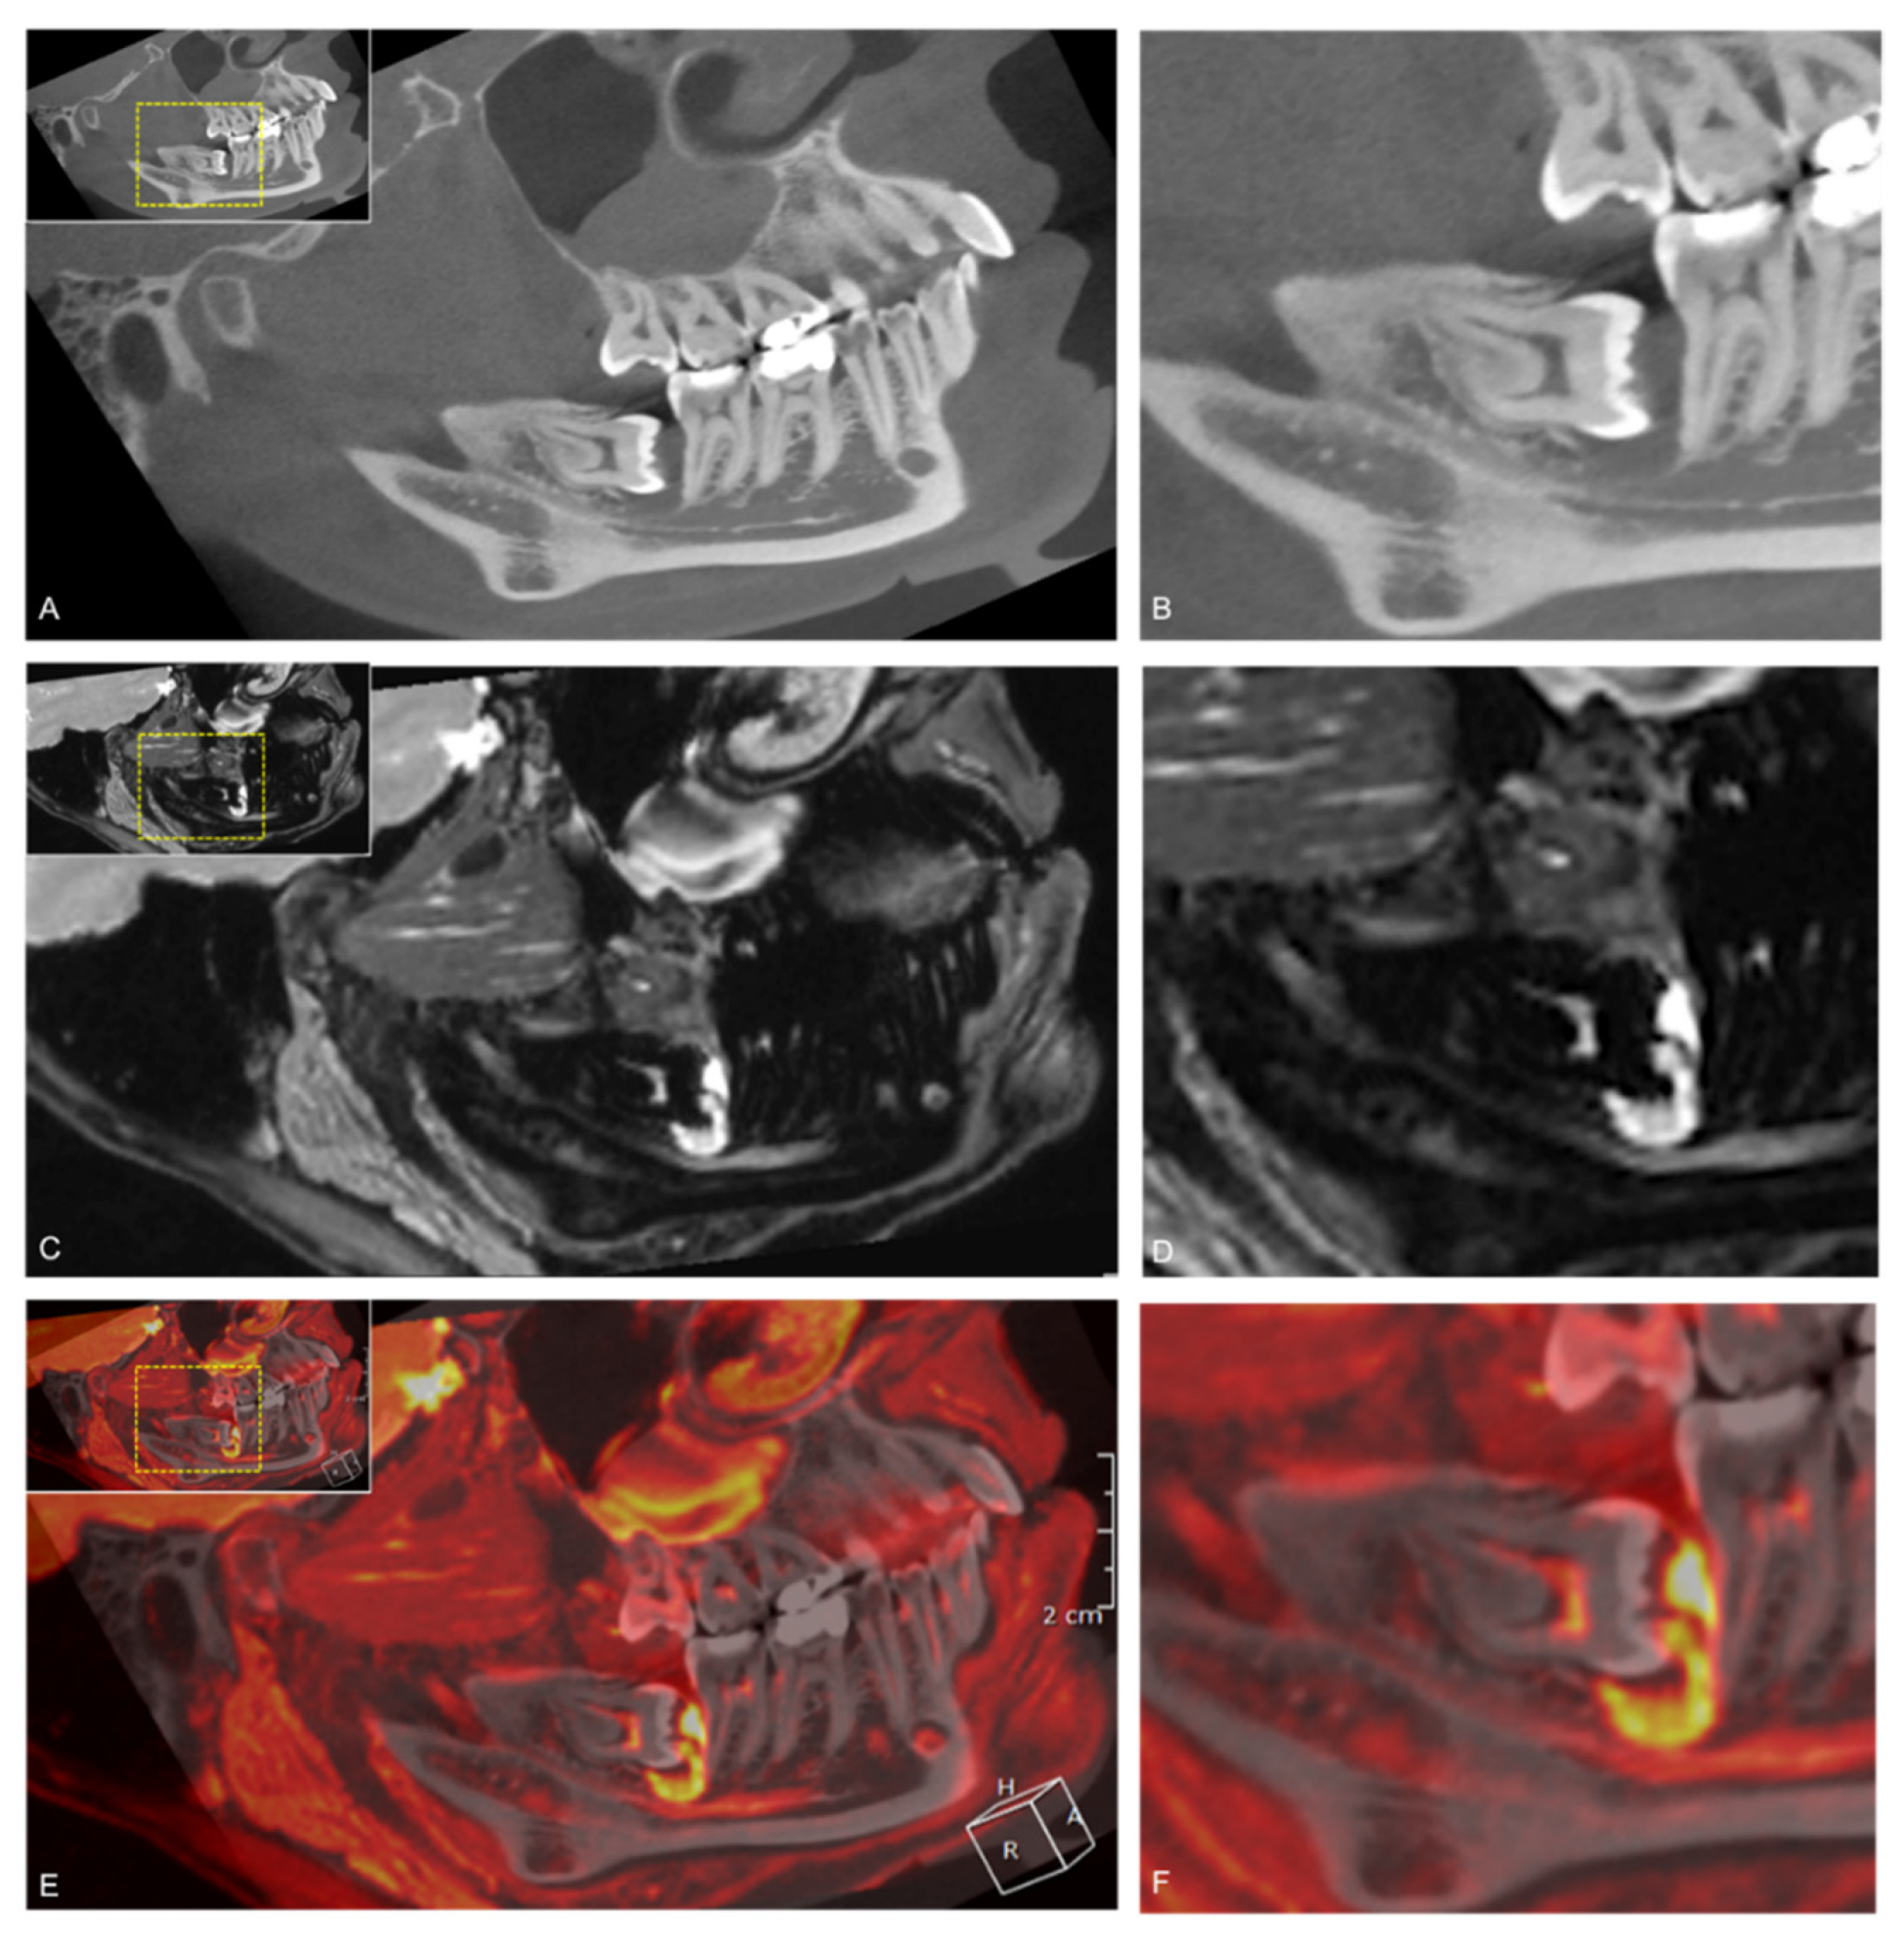

Figure 8. Fusion of study participant’s 3D-DESS MRI (red) and CBCT (gray). (A) Sagittal CBCT reconstruction showing an impacted mandibular third molar with mesial angulation and surrounding follicular cyst; (C) Sagittal DESS MRI visualizing an inflammatory process originating from the follicular cyst, which impressively displaces the IAN within the IAC; and (E) Fused CBCT-MRI scans visualizing the inflammatory process. For orientation, the dotted rectangles in the corner show the enlarged area in CBCT (B), MRI (D), and fused CBCT/MRI scans (F).

Taking into account the superior visualization of bony tissue in CT (respectively CBCT) in the dentomaxillofacial field and that the NVB does not always completely fill the MC, CBCT and MRI scans were fused to determine the fusion pattern in the retromolar and molar region and to investigate whether an additional diagnostic benefit could be achieved. This study confirms the trends observed by Deepho et al. that there is a tendency for the “small pattern” (21%) to be more prevalent in the retromolar region. Nevertheless, it should be noted that the “same pattern” was most frequent in the retromolar (72%) and molar (76%) regions [23]. The large pattern was observed in only 7% of the cases, which is most likely explained by insufficient fusion or insufficient MRI image quality due to motion artifacts. The IAN not filling the MC’s complete volume could explain the different positional relationships in both image modalities due to the minimal difference in IAN position in MRI images compared to CBCT images. It is essential to consider that the fused CBCT/MRI images in this study could not be obtained only by automatic registration function. It was necessary to correct the fusion manually through trial and error to allow the best possible evaluation. Therefore, we can only confirm the need for a perfect automatic fusion algorithm from other studies [23]. However, compared to the MRI protocols used in other studies, we achieved a much better image quality and more accurate evaluation using 3D-DESS MRI protocol. Compared to CT or MRI imaging alone, the use of fused CBCT/MRI images in these borderline cases might offer advantages to the standard preoperative radiological assessment. In cases where inflammatory processes could be detected in the MTM region, MRI and fused CBCT/MRI scans provide a diagnostic advantage with substantial reliability (inter-reader κ = 0.66, intra-reader κ = 0.668), independent of the readers’ experience. This confirms the trends of previous studies that MR imaging is superior in visualizing soft tissue disease, such as periodontitis, even before any osseous defect occurred (Figure 8) [45].